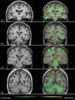

Polycystic osteodysplasia with progressive dementia

Polycystic lipomembranous osteodysplasia with sclerosing leukoencephalopathy is a rare disease characterised by early-onset dementia and multifocal bone cysts. It is also known as Nasu–Hakola disease. [Source: Wikipedia ]